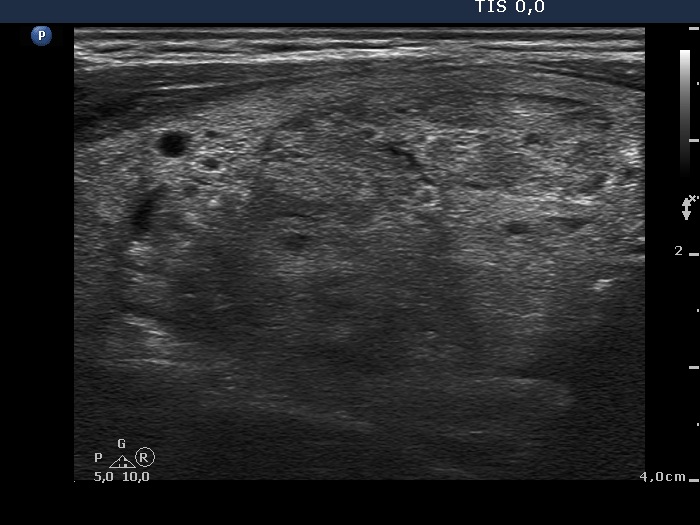

Ultrasonography. Both lobes were composed of multiple nodules of different echogenicities including cystic ones and a large hyperechogenic lesion in the lower part of the right lobe. Except for a moderately hypoechogenic nodule in the dorsal part of the left lobe, the lesions had no oncological significance. The extranodular part was echonormal.

Cytology was performed form the moderately hypoechogenic nodule in the dorsal part of the left lobe and resulted in benign lesion.